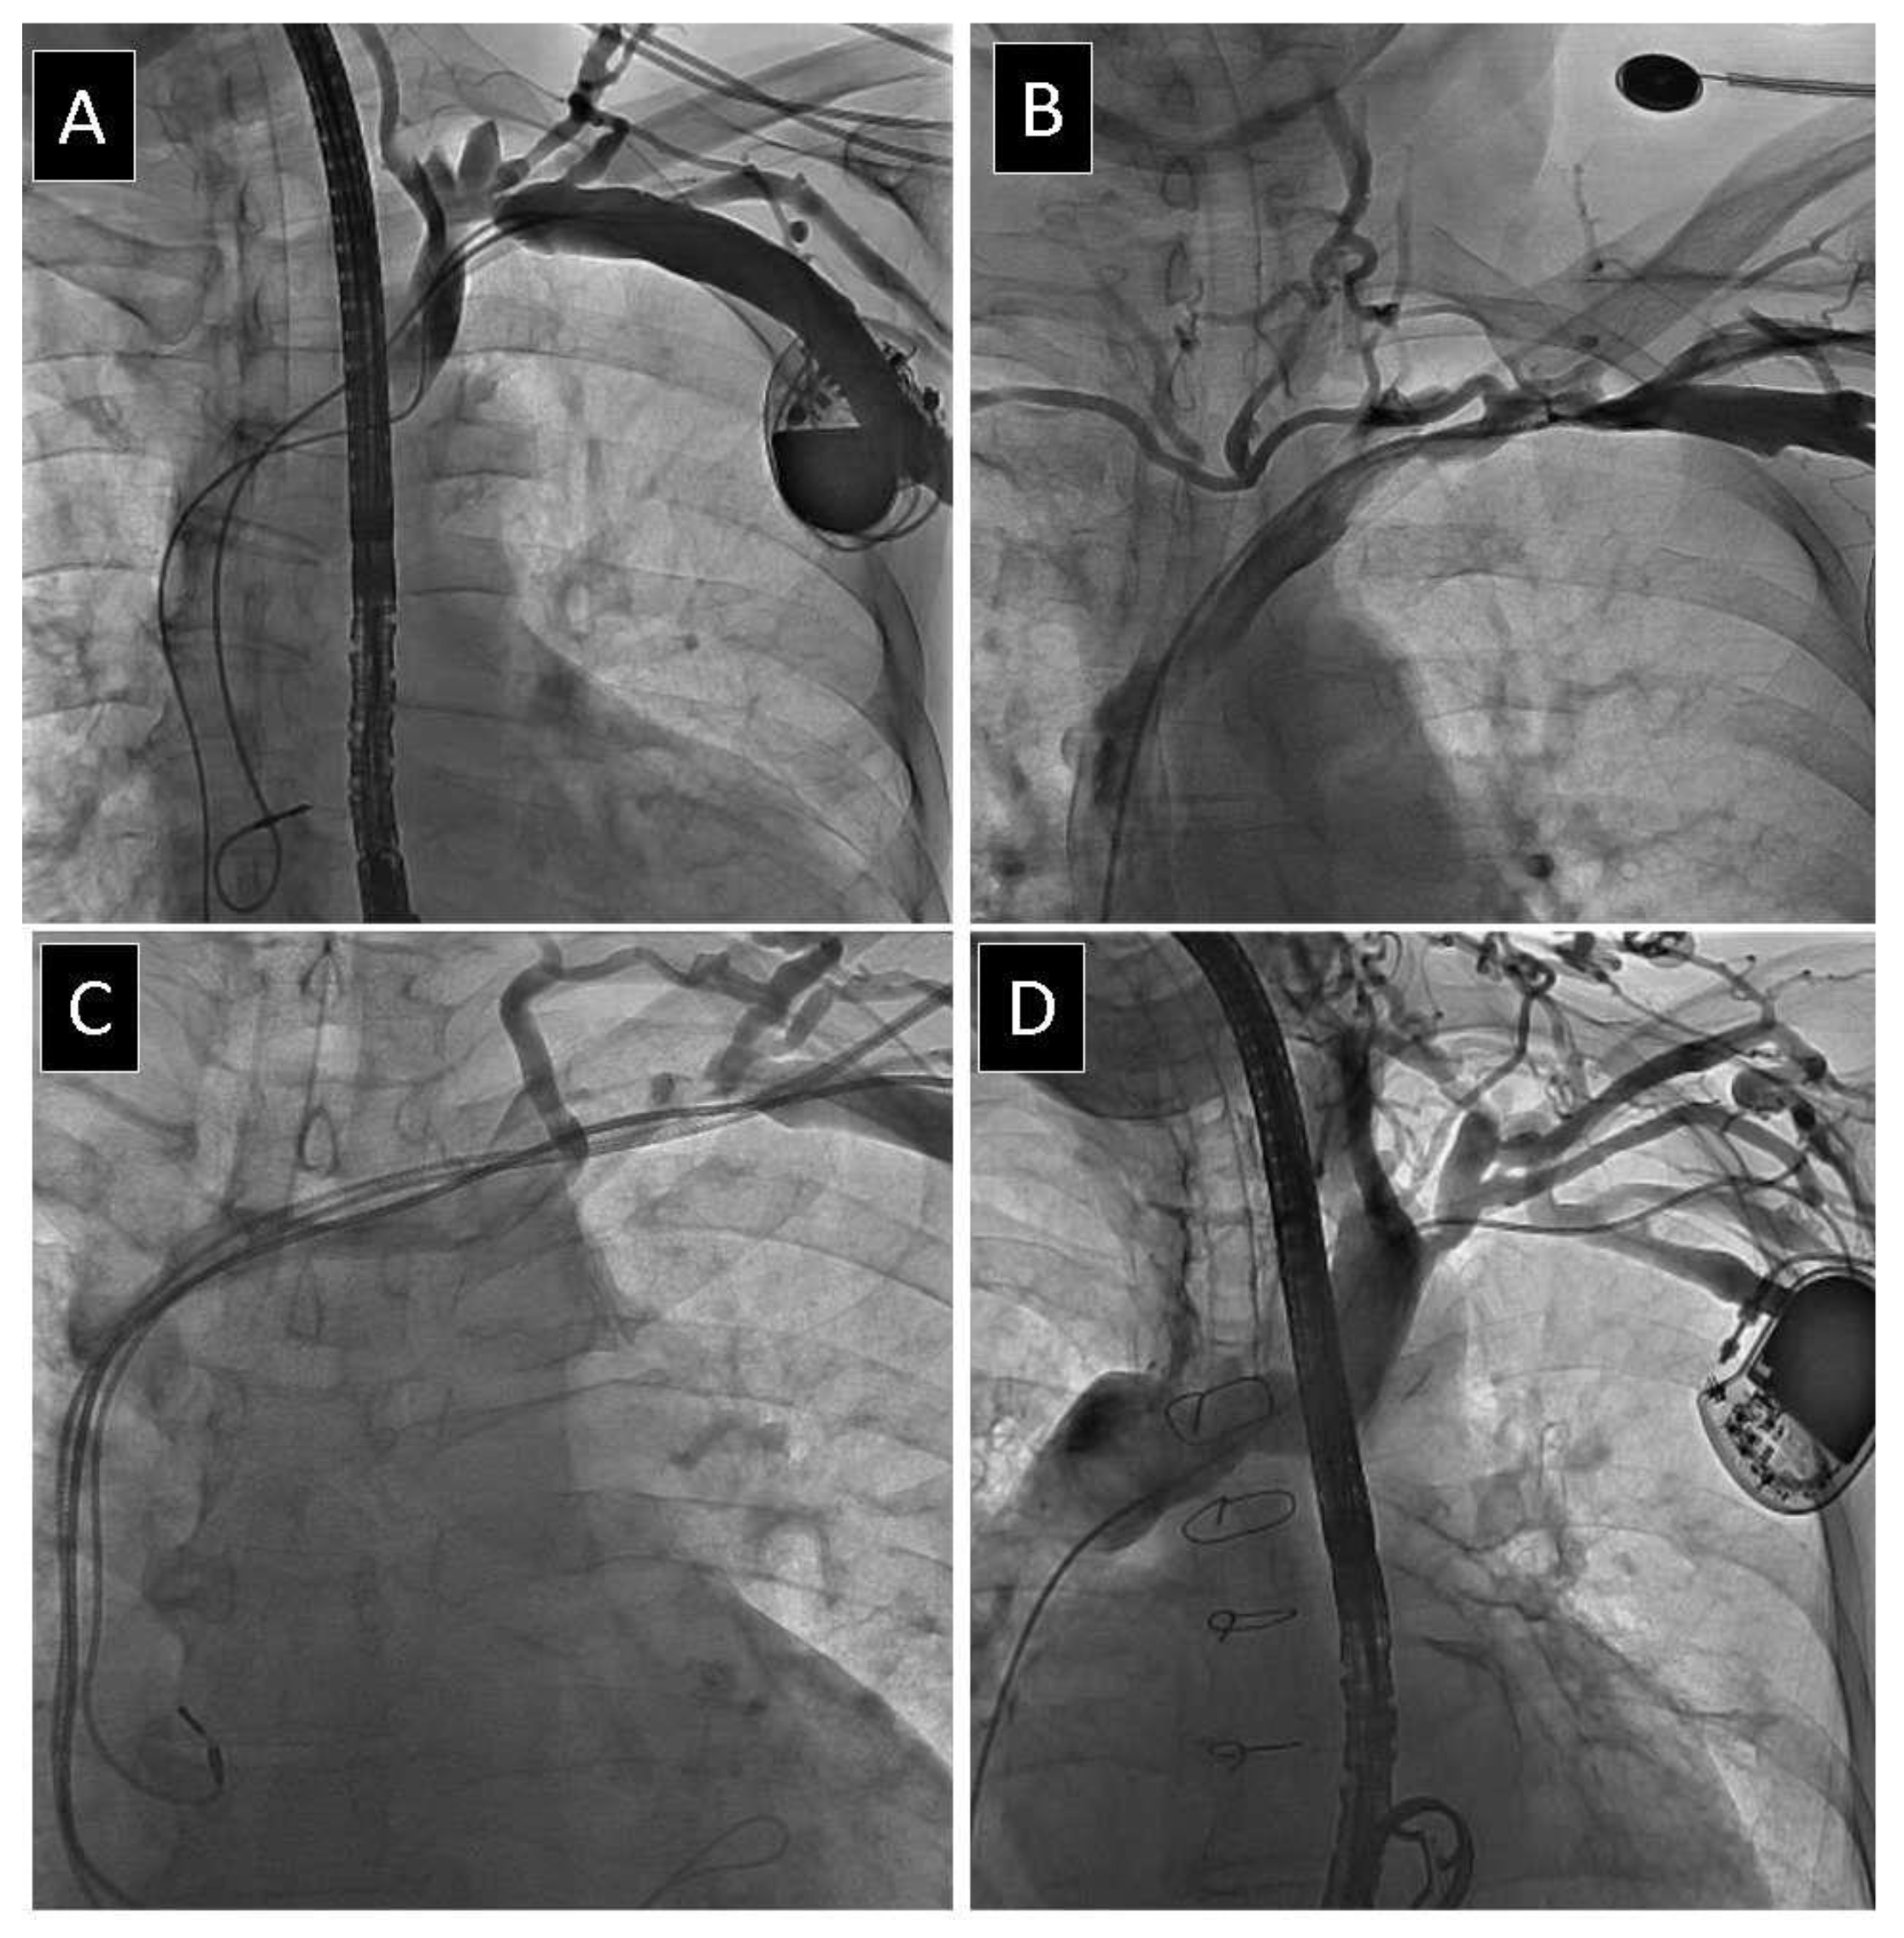

2.2. Venography

2.3. Lead Extraction Procedure